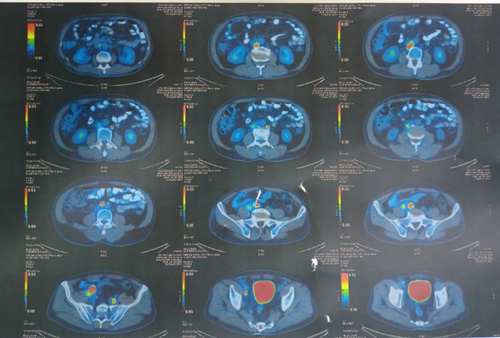

Hình 4: Hình ảnh các hạch ổ bụng tăng chuyển hoá FDG

- Nhiều hạch ổ bụng quanh động mạch chủ, hạch chậu trong 2 bên, chậu ngoài bên trái, hạch lớn kích thước 39x40mm, tăng chuyển hoá FDG.